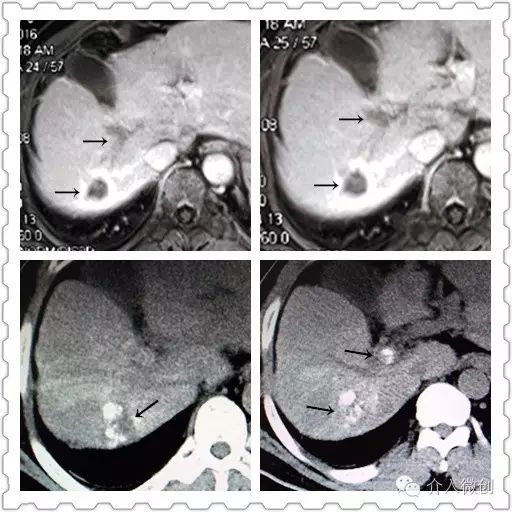

射频消融后1个月复查MRI提示病灶完全消融,边缘可见胆汁瘤,患者无发热、黄疸等不适。但近膈顶部可见2个小结节新发病灶,甲胎蛋白(AFP:244ug/ml)亦未明显下降。

针对新情况,为该患者制定治疗计划:肝动脉化疗栓塞术+射频消融术控制肝内新发瘤灶,并联合碘125放射性粒子植入控制门脉右支癌栓。

DSA造影显示右肝膈顶可见新发病灶肿瘤染色

CT引导下肝癌射频消融术+门脉癌栓放射性粒子植入术,术后2周复查肝脏MRI提示肝内病灶得到有效控制,甲胎蛋白(AFP:14 ug/ml)亦明显下降,术后1个月甲胎蛋白降至正常范围(AFP:3.9 ug/ml)。

射频消融+放射性粒子植入